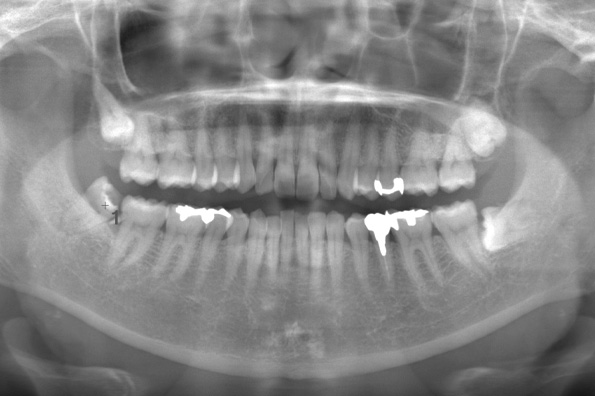

| 治療方針 |

初めに右下の奥歯が痛いとのことでご来院されました。 右下の親知らずと7番目の歯がカリエスになっていたため、まずは右下の親知らず抜歯と7番目の感染根管治療を行いました。左上下の親知らずもカリエスになっているため、今回抜歯を行いました。 |